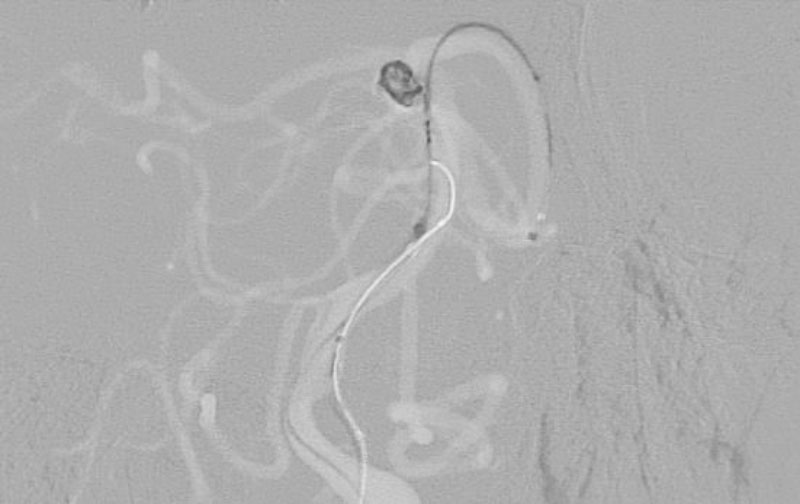

'25年10月

くも膜下出血

前交通動脈瘤破裂

40代

大阪府の病院

No.1589 手術前

No.1589 手術中

No.1589 手術後